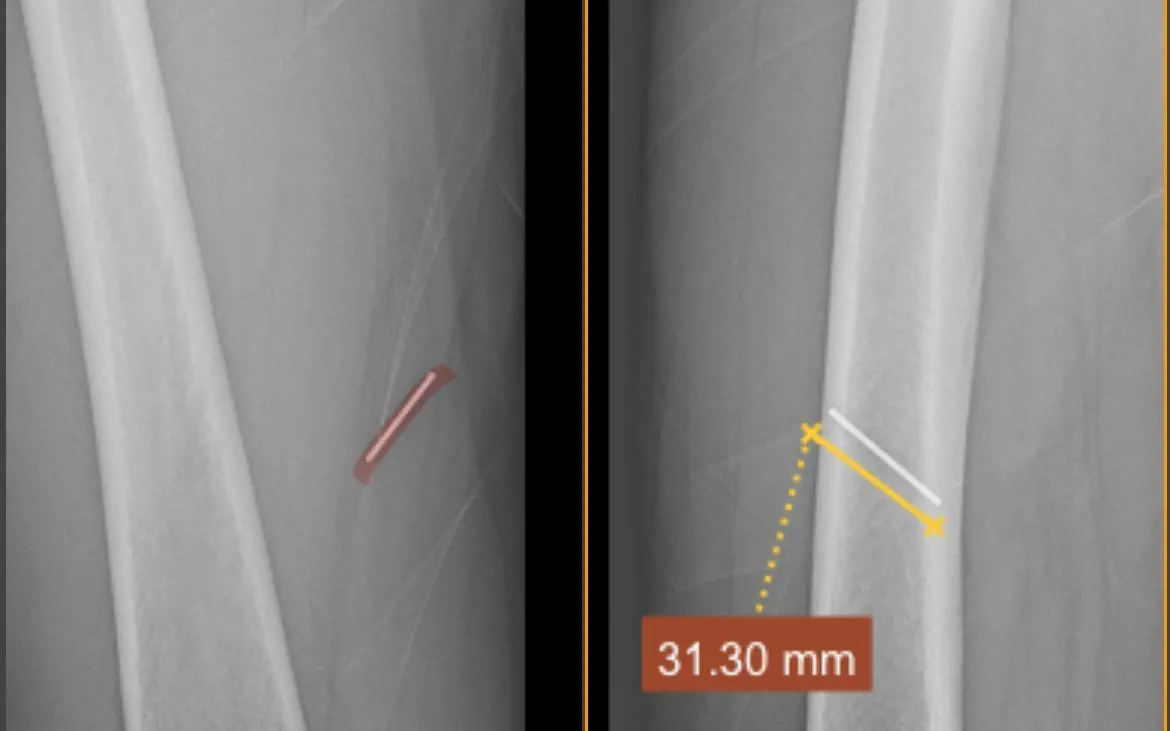

Bệnh nhân nam, 63 tuổi, làm nghề thợ mộc. Trong quá trình lao động, bệnh nhân không may bị súng bắn đinh bắn một chiếc đinh kim loại vào mặt trong đùi. Dị vật nằm sâu trong tổ chức mỡ và cơ, tiềm ẩn nguy cơ tổn thương mô mềm, nhiễm trùng và biến chứng nếu không được xử trí đúng cách.

Ngay sau khi tiếp nhận, các bác sĩ đã khai thác bệnh sử, thăm khám lâm sàng và chỉ định các phương tiện chẩn đoán hình ảnh nhằm xác định chính xác vị trí, độ sâu và hướng đi của dị vật. Trên cơ sở đó, ekip Khoa Ngoại tiến hành thủ thuật lấy dị vật với sự hỗ trợ của trang thiết bị chuyên môn.